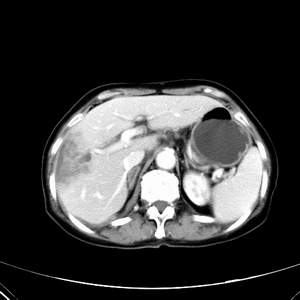

患者,女性,77岁,右上腹胀痛月余。afp正常。ca125升高。即往无肝炎病史。

肝右叶病灶是胆管细胞癌吗?门静脉右支癌栓形成?右侧肾上腺有问题吗?

最后5幅图片是延时7分钟的。门静脉右前支内有充缺吗?如有,肝血管瘤不好解释。

病灶渐进性向心性强化,延时病灶中心见条片状高密度影,局部见肝包膜回缩征,结合病人无肝炎病史,考虑肝右叶胆管细胞癌,门脉右支癌栓形成。